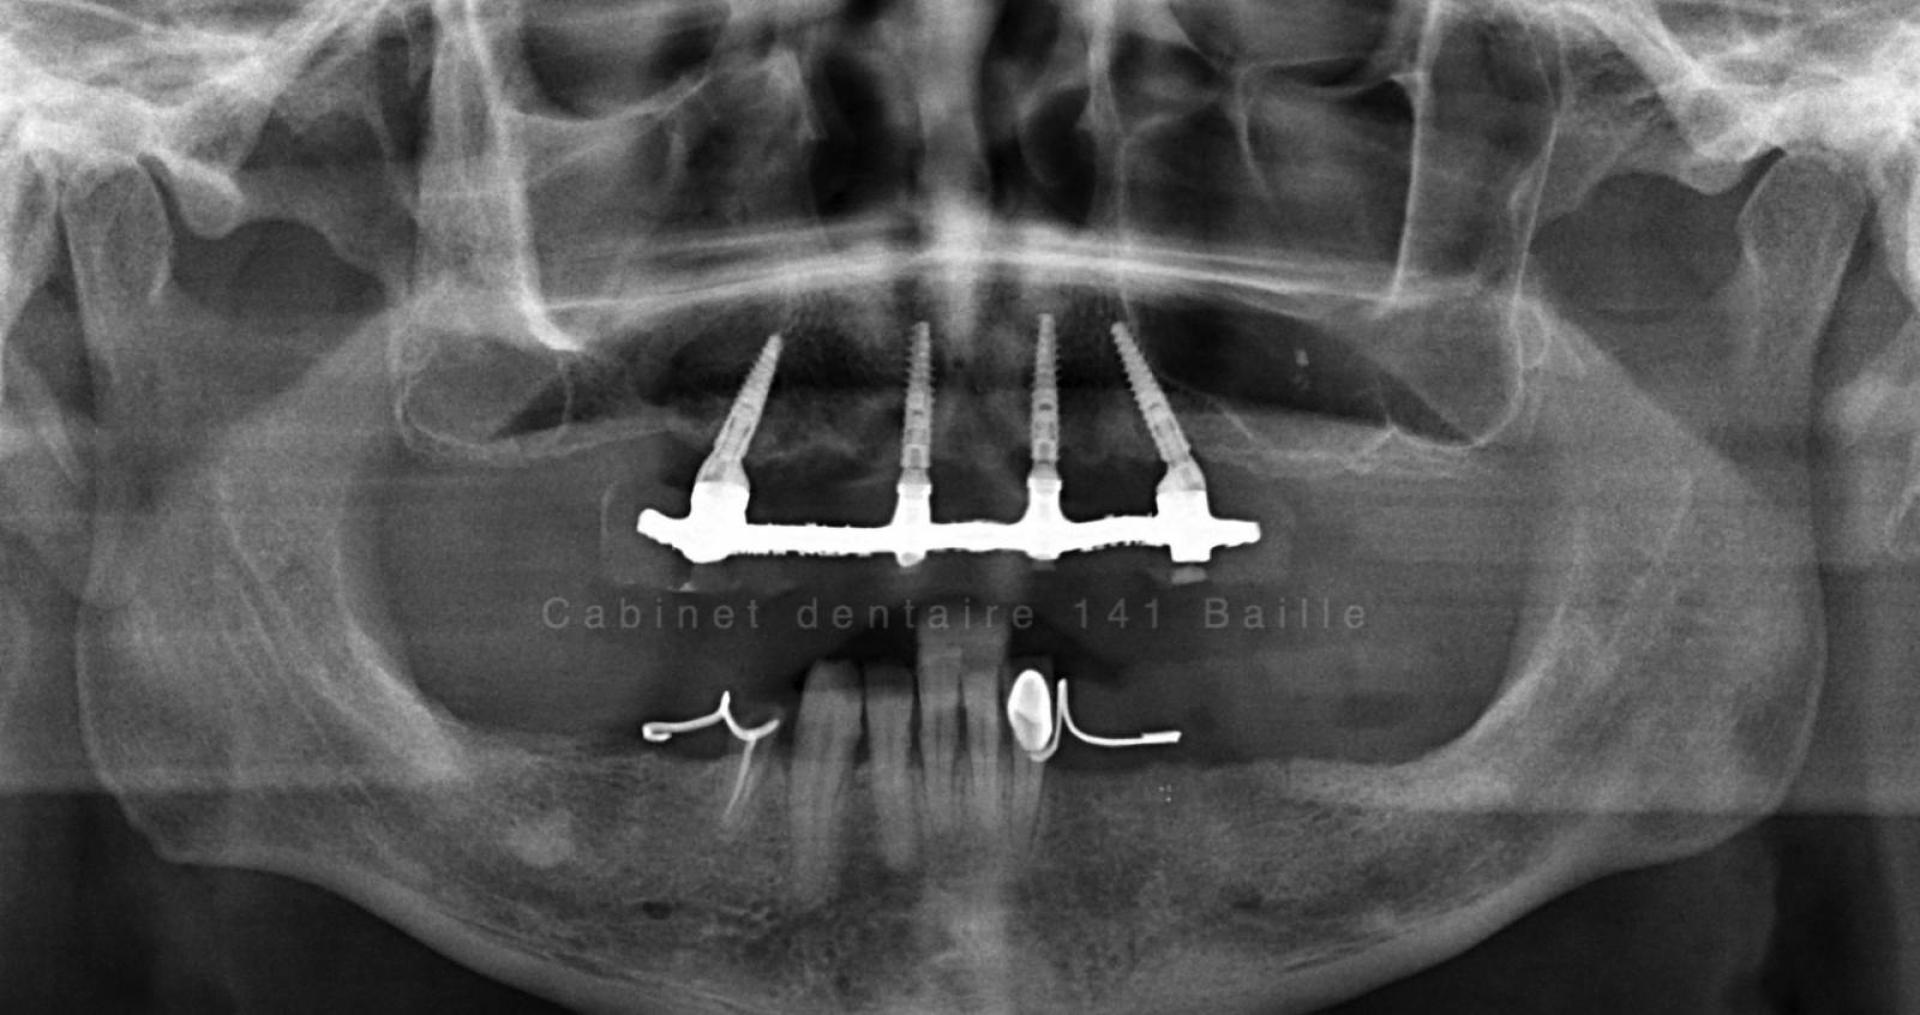

all on 6 chirurgie guidée par spécialiste all on 6 implantologie dentaire

Chirurgie implantaire guidée : l’expertise d’un spécialiste en implantologie à Marseille pour les techniques All-on-4 et All-on-6

Spécialiste implantologie à Marseille, expert All-on-4 et All-on-6. Découvrez comment la chirurgie implantaire guidée offre précision, sécurité et résultats immédiats.